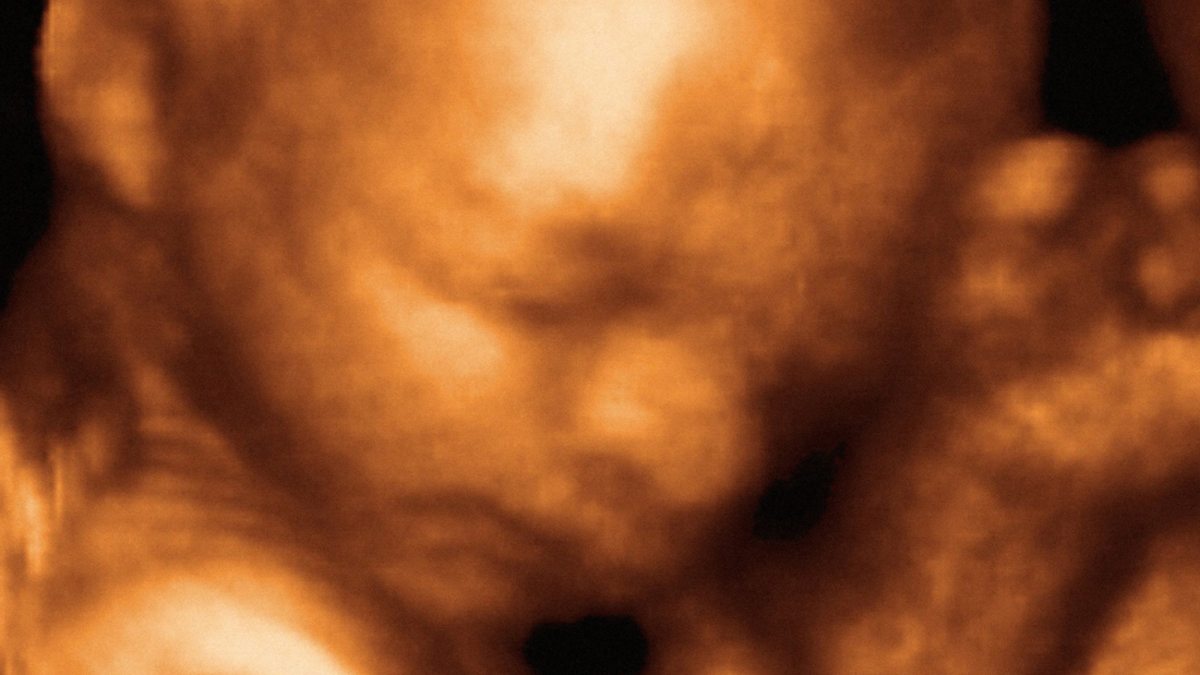

Photo: an ultrasound of a foetus in the womb. Credit: Science Photo Library.